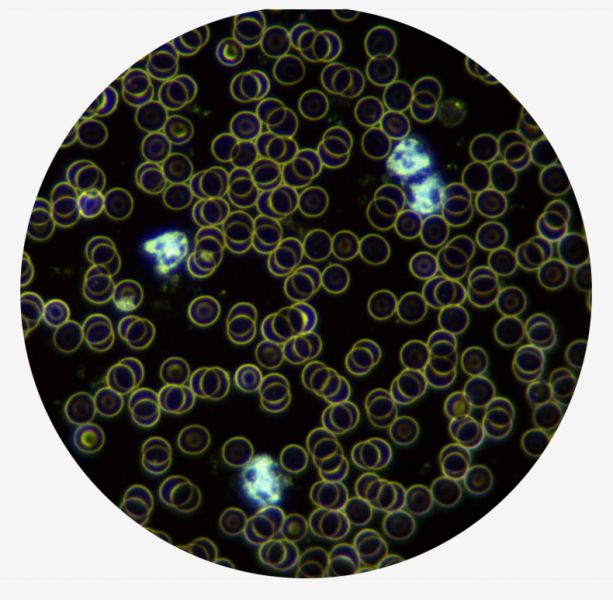

H-500 je silným antioxidantom. Po vložení do vody vytvára zásaditú živú vodíkovú vodu. V našom organizme to spôsobuje, že červené krvinky erytrocyty získajú záporný náboj a tým sa od seba odtláčajú.

Červené krvinky roznášajú kyslík po celom tele, hlavne do mozgu. Tým, že sa od seba odlepia, viď foto živej kvapky krvi spod mikroskopu, človek nie je zrazu unavený, ospalý. Získa veľa energie.

Toto sú reálne fotografie krvi spod mikroskopu, na ktorých pekne vidno:

- Ako vyzerá nezakyslená krv (obr. vľavo) – červené krvinky sú voľné a majú pekný okrúhly tvar (ľahko prenášajú kyslík)

- Ako vyzerá zakyslená krv (obr. vpravo) – červené krvinky sú zlepené, sploštené a vytvárajú zhluky